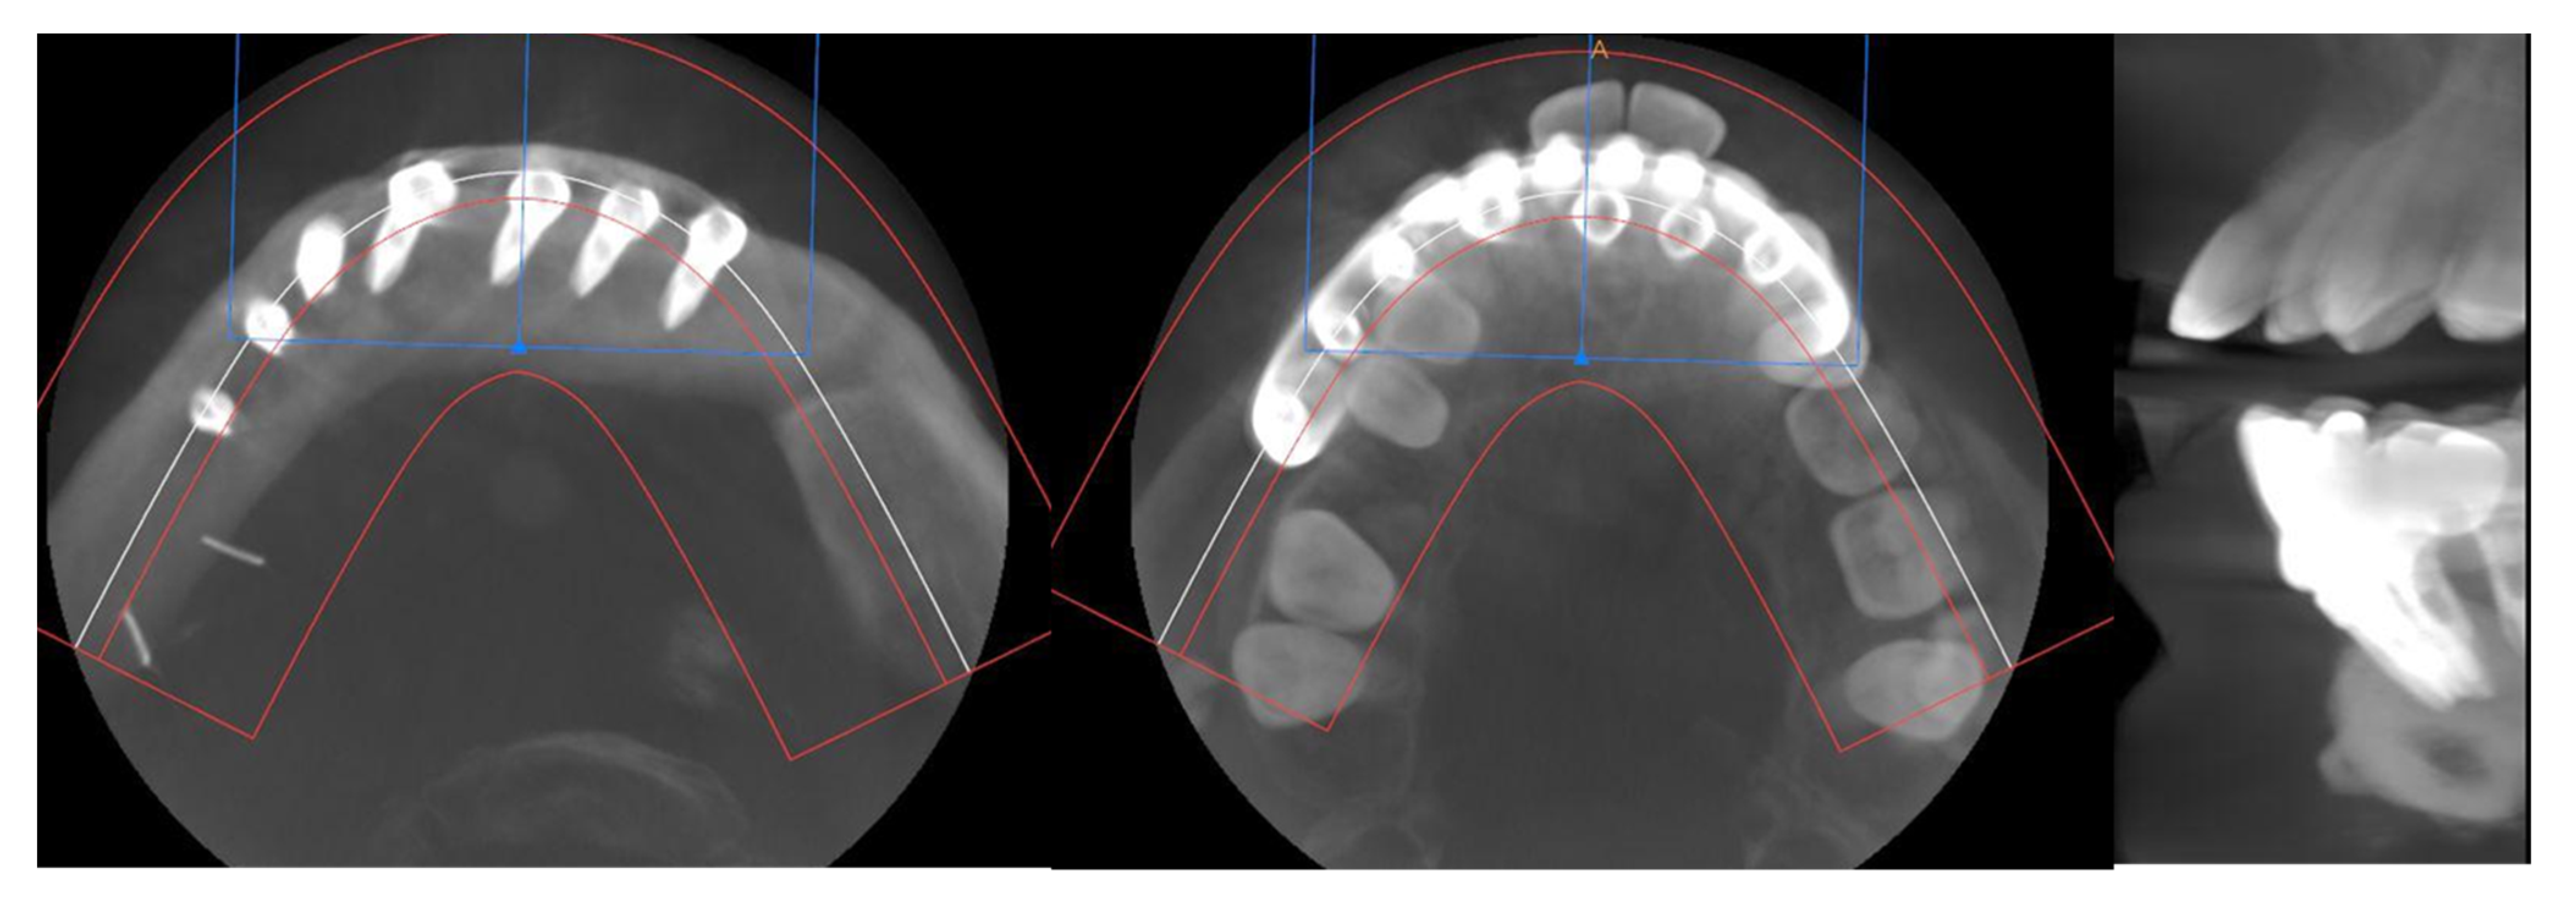

Simultaneously, a cortico-cancellous graft of the left anterosuperior iliac crest was obtained. The graft was fixed to the fibula using the CAD/CAM titanium mesh and 1.5 mm screws (Figure 5B). There was no intraoral exposure of the graft and an increase in the vertical dimension of the fibula was achieved and demonstrated by panoramic radiograph and CT scan (Figure 6A,B and Figure 7A,B).

CT Scan and CBCT were performed in the postoperative follow-up, and bone volume and bone resorption (Figure 13 and Figure 14) were evaluated by the Radiology Department of the hospital. A morphing reconstruction was performed to compare the lower facial third showing an improvement in the aesthetic profile and facial projection (Figure 15).

Figure 7. Postoperative CT scan. (A) Axial CT Scan demonstrating the stability of the transverse dimension of the fibula with respect to the remnant mandible. (B) The three-dimensional preservation of the iliac crest graft with CAD/CAM mesh makes it possible to double the height of the fibula.